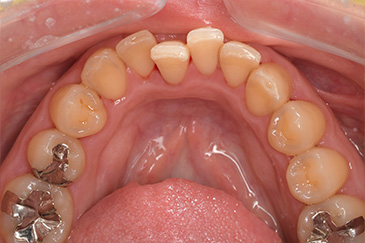

Before

After

基本情報

| 年齢・性別 | 30代・女性 |

| 主訴 | 定期検診 |

| 治療内容 | PMTC |

| 治療期間 | 60分 |

| 治療費 | 5,750円 |

| リスク・副作用 | しみる可能性があります。 |

| 治療方針 | PMTCでステインの除去。 |

| 担当者所見 | ステインが付きやすいため、3カ月毎の定期検診で除去する。 |